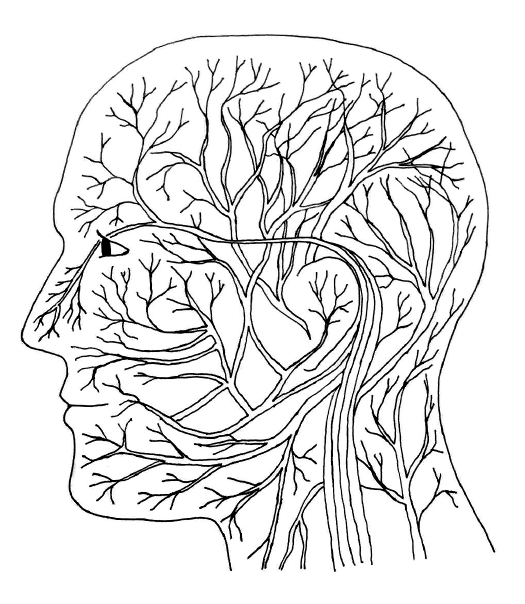

在第二篇的第三章談夢和情緒時,我已經提過「情緒腦」,也就是邊緣系統(limbic system)——位在中腦和大腦之間邊緣地帶的腦部組織。情緒腦,是大腦接收資訊的過濾網。它既影響情緒,為認知加上一層情緒的色彩,而讓我們不可能客觀。

在情緒腦,有一個部位叫做下視丘(hypothalamus)。下視丘作為神經系統和內分泌之間的橋梁,影響腦下垂體這個內分泌的中樞,而進一步影響全身的內分泌。同時,也進一步調控交感神經和副交感神經的作用。

假如你還記得,我們的日週期是跟著太陽走,才有一個接近24小時的日週期,而依照白天和晚上的差別,有不同的生理的反應和運作。幾十年前,沒有人想過,那麼複雜的週轉,是由腦部的單一部位在控制,而這個部位在情緒腦裡。

就在下視丘裡,有一個視交叉上核(suprachiasmatic nucleus, SCN)在控制日週期。如果你還記得,解剖學家會稱之為「核」的腦部組織,指的就是神經細胞特別密集的地方。

回到陽光的作用,舉例來說,在眼睛的視網膜上有一些神經,直達啟動日週期的中樞,也就是前面提過的視交叉上核。這些視神經上有一種色素,叫做黑視素(melanospin),對波長較短的藍光特別敏感。這種藍光特別能活化視交叉上核,而視交叉上核又直接通往松果體,去抑制松果體的活性,不讓它產生褪黑激素。(前面提過,褪黑激素會讓人有睡意,體溫下降,讓身體知道該睡覺了。)